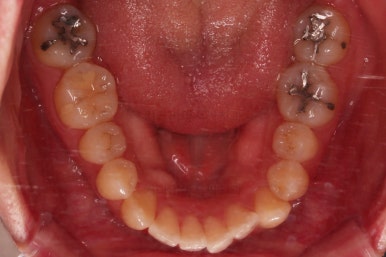

초진 시, 입안의 모습입니다.

좌측 송곳니가 덧니처럼 튀어나가 있고, 송곳니 옆의 작은 억므니가 안으로 쏙 들어가서 덧니 느낌이 더 강조되어 보이네요.

위아래 앞니가 긴밀하게 겹침이 없는 약간의 개방교합(오픈바이트, Openbite) 경향이 보입니다.

철사가 들어가니 삐뚤한 치열이 더 강조되어 보이네요.